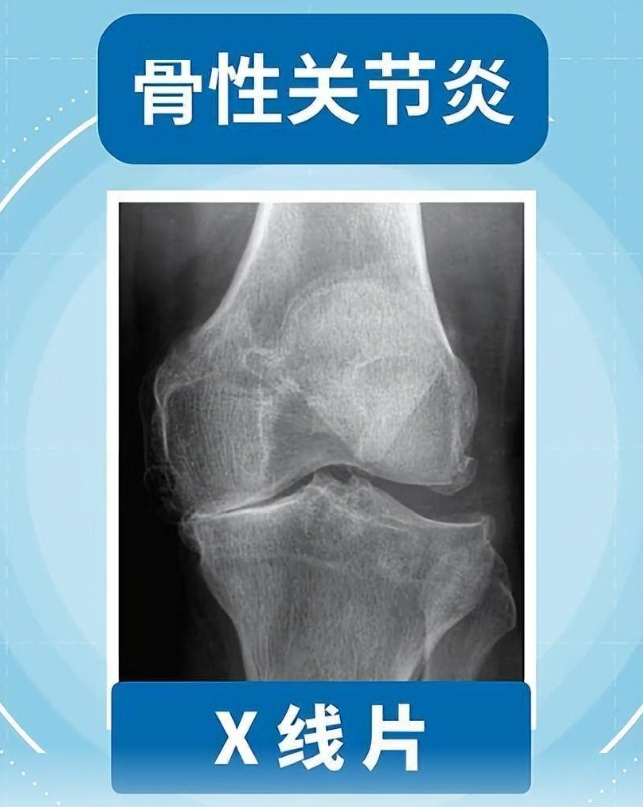

腾讯新闻网页版:且行且珍“膝”!膝盖脆弱的你,请收好这份护“膝”秘籍